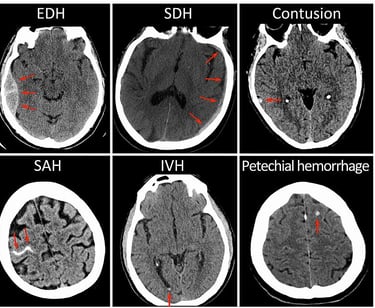

We are excited to announce the launch of our internal research collaboration with University Hospital L. Pasteur in Košice. This foundational project seeks to explore AI applications in diagnosing brain hemorrhages, a critical component in managing Traumatic Brain Injuries (TBIs).This project aims to lay the theoretical groundwork for AI models designed to support brain hemorrhage diagnosis. At TRL 1, our focus is on establishing foundational concepts and identifying the ways an AI model might assist in detecting and classifying different types of brain hemorrhages on CT scans in the future. TBIs are a leading cause of mortality and long-term disability globally. In the acute setting, brain hemorrhages resulting from TBIs require precise and timely diagnosis to guide life-saving interventions.

Traumatic brain injuries (TBI) are among the most severe global health challenges, often leading to permanent disabilities or fatal outcomes. The ability to deliver timely and accurate diagnosis is critical in shaping patient outcomes, as rapid intervention significantly improves survival and recovery chances. However, TBI diagnostic accuracy is frequently challenged by the demanding nature of emergency settings. Physicians must assess CT images under intense time pressure, where subtle signs of bleeding can be easily missed—especially in high-stress conditions like overnight shifts and after extended hours.

TRL 1 – Establishing a Conceptual Foundation:

In this early TRL 1 phase, our focus is theoretical, aiming to lay down a robust framework to assess AI's potential in enhancing TBI diagnosis. Working closely with clinical experts at L. Pasteur University Hospital, we are evaluating current diagnostic approaches and exploring AI’s role in supporting clinicians with “second read” capabilities, to reduce diagnostic variance. By thoroughly analyzing current AI methods and conceptualizing novel models, our goal is to validate AI’s potential to enhance diagnostic precision and reduce time to decision, particularly for critical and complex cases.